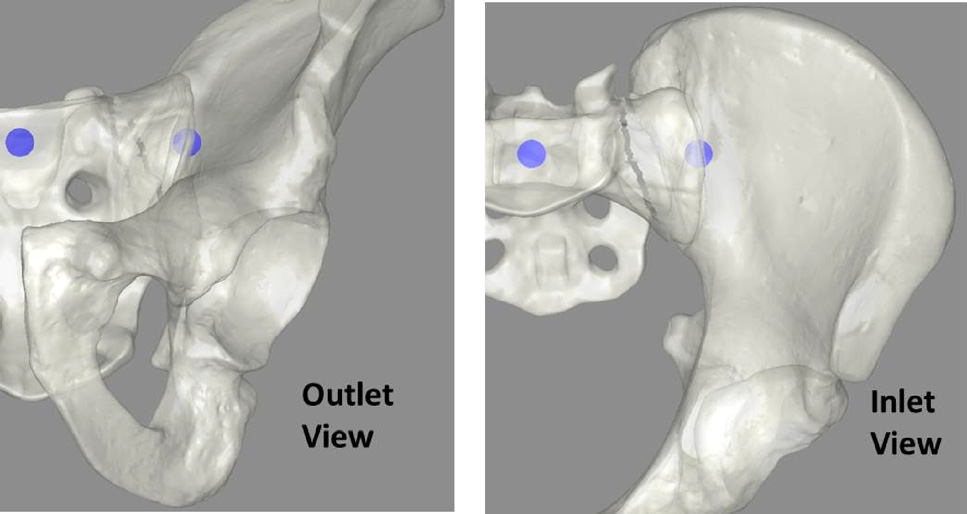

骶髂螺钉固定的手术技术是一种微创手术,涉及将导丝垂直置于骶髂关节并穿过骶骨体中线[14]。使该手术具有挑战性的因素包括:首先,用于正确放置植入物的通道可能非常狭窄。该通道周围有多条脆弱的神经根和脊髓。据报道,植入物放置不当的发生率在18%至24%之间[15–18]。此外,患者之间的骨盆解剖结构差异很大,要求外科医生根据每位患者的情况调整植入路径,甚至导致部分患者无法接受该手术。

文献检索揭示了外科医生通常遇到的解剖变异范围内理想植入物位置的参数。一项研究分析了一组骨盆扫描,以相对于解剖变异定义理想路径和可接受的通道参数[19]。该分析将工作体积定义为穿过骶骨体且不与神经根相交的圆柱形通道。分析表明,在多种骨盆解剖结构中,该通道的平均直径为14 mm(0.55 in.),平均长度为150 mm(5.91 in.)[19]。

该通道定义了导丝在骨骼内的位置,但外科医生还必须经皮引导导丝穿过周围的软组织。因此,为了完整定义该手术的工作体积,还必须考虑导丝穿过软组织到达骨表面的路径。在我们的实现中,设计了一个软组织包膜,其骨表面与摄像头可见导丝区域之间约有76毫米(3英寸)的材料间隔。导丝到达骨骼内该通道所占据的空间由此形成一个平截头体,前端宽度为30毫米(1.18英寸),深度为76.2毫米(3英寸),后端宽度约为60毫米(2.36英寸)(图4)。该工作体积使系统能够准确跟踪通过骶骨体安全通道内的任何导丝。

为了向住院医师显示正确的图像,对模拟器的软件进行了调整。使用可视人计划的CT数据VR 1生成了该手术中使用的透视图像(图6)。该手术使用三个主要透视视图:出口视图、入口视图和侧位视图。入口视图和出口视图是用于引导导丝导航的主要视图。这两个视图相对于患者处于斜角,使得导丝轨迹和必要调整难以判断。学会在这两个视图中正确评估导丝轨迹被认为是该手术的主要技能之一。